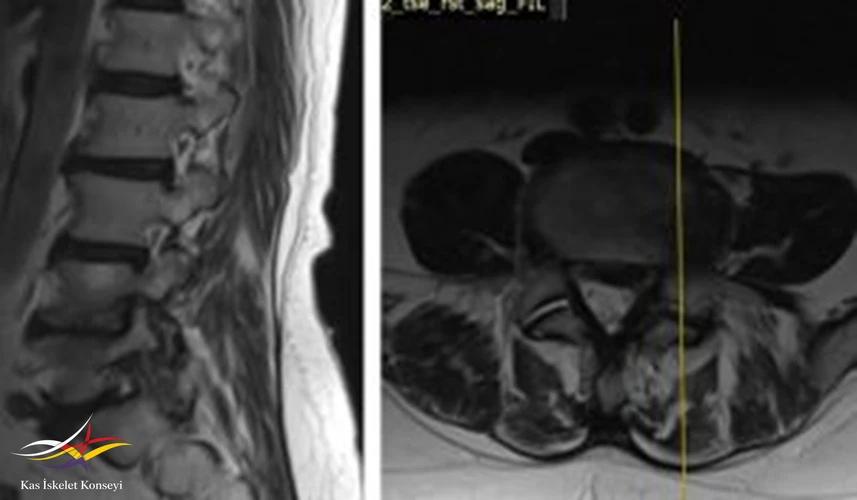

İncelemeler: Lomber MRG: L4-5 diskal bulging ve sol foraminal stenoz var. Kalça MRG istendi, iki yanlı trokanterik bursit rapor edildi.